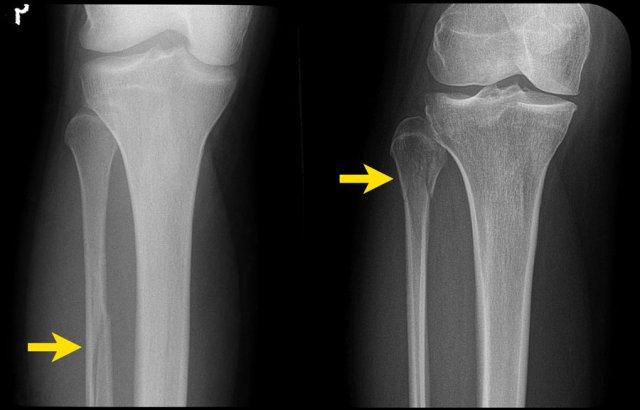

Hình bên trái là một ví dụ khác về gãy xương hai mắt cá không ổn định giai đoạn 2 Weber A.

Hình bên phải cho thấy đường gãy thẳng đứng của mắt cá trong (mũi tên). Đây luôn là giai đoạn 2 và không ổn định. Điều này có nghĩa là giai đoạn 1 đã xảy ra trước đó, vì cơ chế chấn thương luôn tuân theo trình tự nghiêm ngặt: giai đoạn 1 trước, sau đó mới đến giai đoạn 2.

Vòng ổn định bị phá vỡ ở hai vị trí (cuộn ảnh để xem).